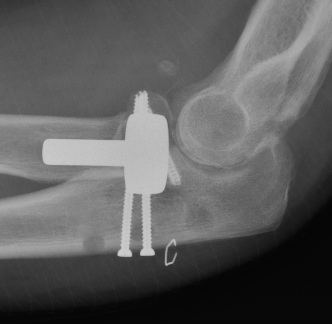

Radial head replacement with lag screw fixation of Type II coronoid

terribleterribleterribleterrible

Radial head replacement with lasso fixation of small coronoid fragment